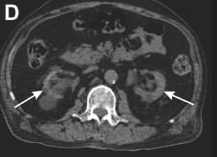

Abdominal CT – white arrows indicate CKD renal changes.

A 66 year old man with CKD on hemodialysis presented with bilateral amaurosis for 2 months. Fundoscopy was normal. CT revealed bilateral optic nerve sheath calcifications. Labs: PTH 105 pg/mL, Ca 12.5 mg/dL, PO₄ 3.8 mg/dL, ALP 192 U/L, 25-OH vitamin D 17 ng/mL. Suggests CKD-related mineral and bone disorder with rare orbital manifestation. Differentials: meningioma, glioma, phthisis bulbi, prior hemorrhage.